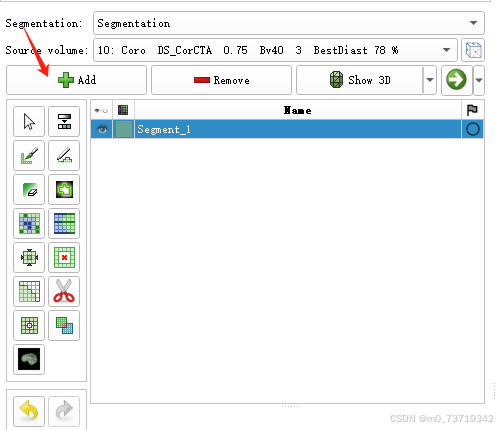

点击segment Editor

点击Add创建第一个标签

依次点击如下按钮